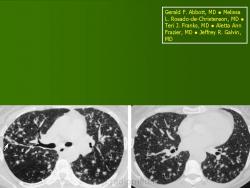

Наиболее часто изменения выявлялись в височных костях (21), несколько реже в лобных (16) и теменных (14). Реже всего поражалась затылочная область (4), орбита (3), сосцевидные отростки (2). В 44% случаев отмечались сочетанные поражения черепа и других костей, в том числе: ребер (17), подвздошных костей (6), ключиц (4), крыши вертлужной впадины (3), лонных и седалищных костей (3), бедренных (4) и большеберцовых (4). При поражении костей таза, ребер, ключицы определялись разновеликие дефекты, между которыми нередко сохранялись костные перемычки, создающие картину сетчатой или ячеистой структуры. В типичных проекциях гиперостоз улавливался не всегда или был прерывистым. Опорными рентгенологическими симптомами являлись четкие фестончатые контуры очагов, однородность фона, отсутствие включений. Поражения в длинных трубчатых костях (Рис. 2) чаще локализовались в метафизарных отделах проксимальных концов. Деструктивные участки обычно располагались субпериостально, имели овальную или округлую форму, четкие полициклические контуры. Наибольший их размер был направлен вдоль оси кости. Кортикальные слой изнутри истончался или прерывался. Снаружи определялись периостальные наслоения в виде скорлупы, имеющие иногда слоистый характер.

Рис. 3.Рентгенограмма правой голени больного С.В., 5 лет с диагнозом ГКЛ. Очаг деструкции с отеком и инфильтрацией в средней и нижней трети правой большеберцовой кости.